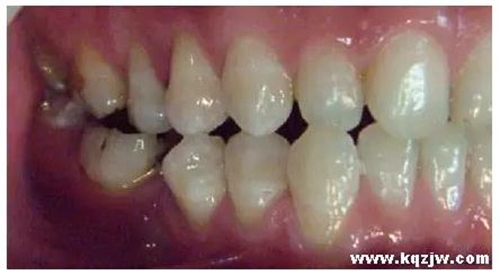

這種咬合接觸的結(jié)果是局部的咬合力集中在凸點(diǎn)接觸的位置,不能被有效分散,可造成受力部位牙體、牙周組織的應(yīng)力集中。最常見(jiàn)的表現(xiàn)是后牙頰舌向呈對(duì)刃關(guān)系,另外還常見(jiàn)于不完全遠(yuǎn)中關(guān)系或不完全近中關(guān)系的情況,此時(shí)從近遠(yuǎn)中方向來(lái)看,上下后牙牙尖之間凸凸相對(duì)(圖3)。

圖3 后牙凸凸接觸關(guān)系